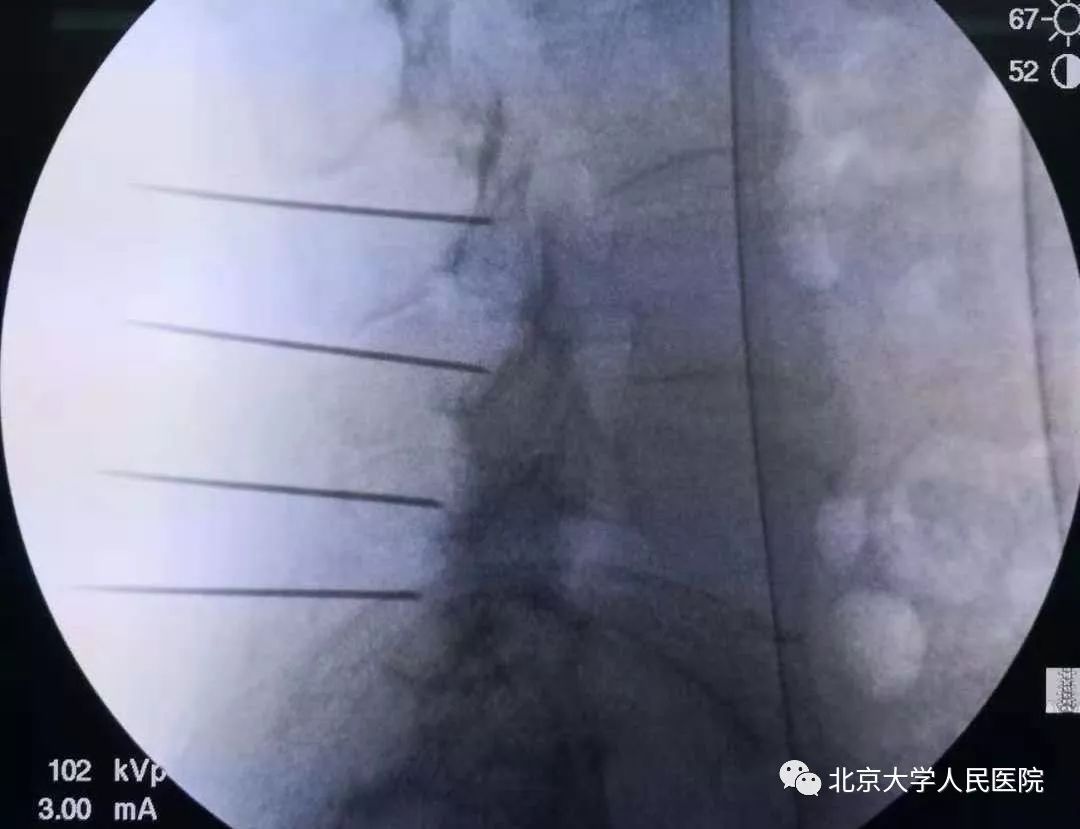

椎体成形术治疗脊柱压缩性骨折

骨质疏松导致骨密度下降,容易并发椎体压缩性骨折。通过向压缩的椎体注入骨水泥,使其恢复初始刚度,能明显缓解椎体压缩骨折引起的胸背部及胸腹部剧烈疼痛。该技术创伤小,即刻效果明显,得到广泛应用。椎体成形术对骨质疏松性脊椎压缩骨折的疼痛,缓解成功率高达90%以上。